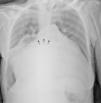

The chest X-ray showed marked cardiomegaly (cardiothoracic ratio 0.92) and splaying of the carina and of the main bronchi (Figure 1).